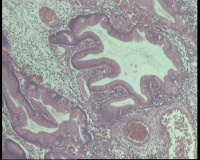

67岁

胃体大弯侧息肉1.5厘米

息肉1.5x1.1x0.8厘米

息肉表面糜烂,炎性坏死,肉芽组织,这个报增生性息肉伴糜烂,肉芽组织形成,请老师看看最后3个图里的2个腺体够非典型增生吗?

增生性息肉

形态符合增生性息肉。